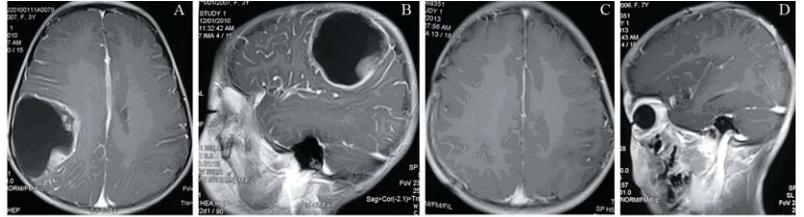

四组胶质瘤患者术后头痛、恶 心、呕吐等高颅压症状消失,癫痫发作得到控制, 意识障碍得到纠正或均恢复正常,偏瘫和偏身感觉 异常均有不同程度的恢复或改善。四组胶质瘤患者 术后Karnofsky≥60比较,见表2。四组胶质瘤患者 术后1周的Karnofsky≥60比较,差异无统计学意义 (χ2=0.339,P=0.95),即术后1周四组患者生活质量 无明显差异;术后1、2年的Karnofsky≥60比较, 差异均有统计学意义(χ2=8.199和7.864,P=0.042和 P=0.049),即术后1、2年ACNU+TMZ+RT组生存质 量明显优于RT组、ACNU+RT 组及TMZ+RT 组; 术后3年的Karnofsky≥60比较,差异无统计学意义 (χ2=2.059,P=0.560),即术后3年四组患者生活质 量差异无统计学意义。

表2四组脑胶质瘤患者Karnofsky≥60比较 Table 2 Comparison of Karnofsky≥60 of glioma patients in four groups |